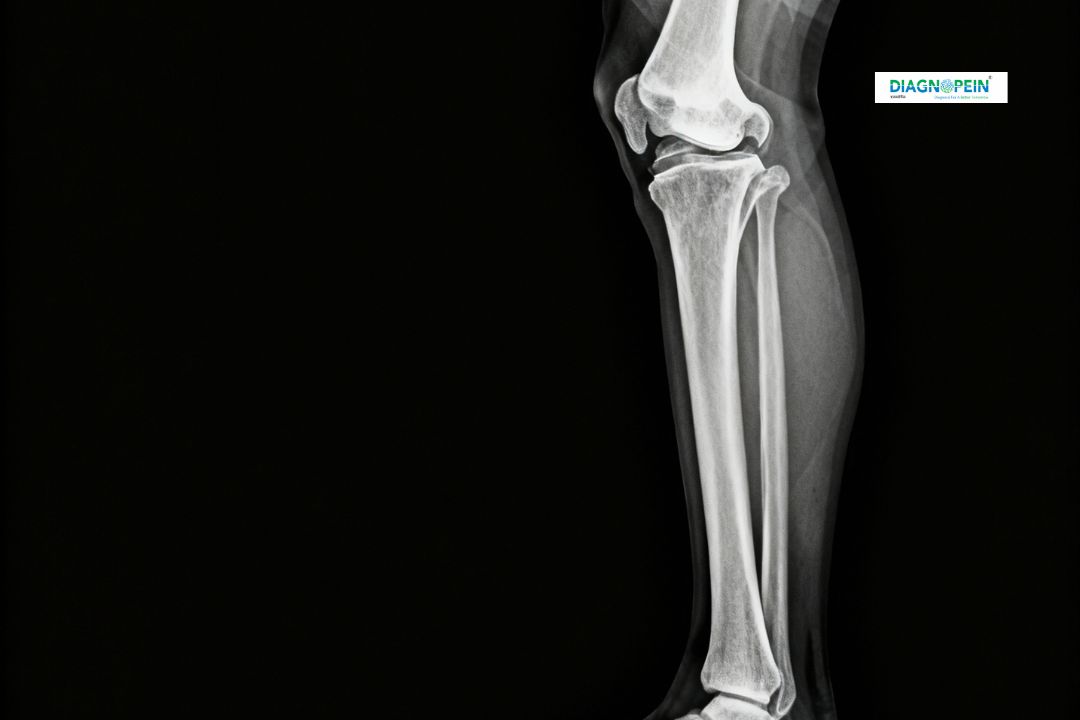

At Diagnopein, Karad, we provide precise X-Ray Leg AP & Lateral imaging services to evaluate bone injuries, fractures, and alignment issues in the leg. This advanced imaging technique captures clear front (AP) and side (lateral) views of the leg bones, including the femur, tibia, and fibula. Using high-resolution digital equipment, our radiology experts ensure accurate results that support effective diagnosis and treatment planning.

An X-Ray Leg AP & Lateral is routinely recommended for patients suffering from pain, swelling, or trauma in the lower limbs. It allows doctors to assess bone structure, locate fractures, detect bone infections, and monitor healing progress after surgery or plaster application.

The X-Ray Leg AP & Lateral plays a crucial role in orthopedic and accident-related diagnosis. In Karad, many patients visiting Diagnopein require this specific X-ray for post-injury evaluation and bone condition monitoring. This test helps doctors visualize both the anterior-posterior and lateral angles of the leg, offering a comprehensive assessment that a single view cannot provide.